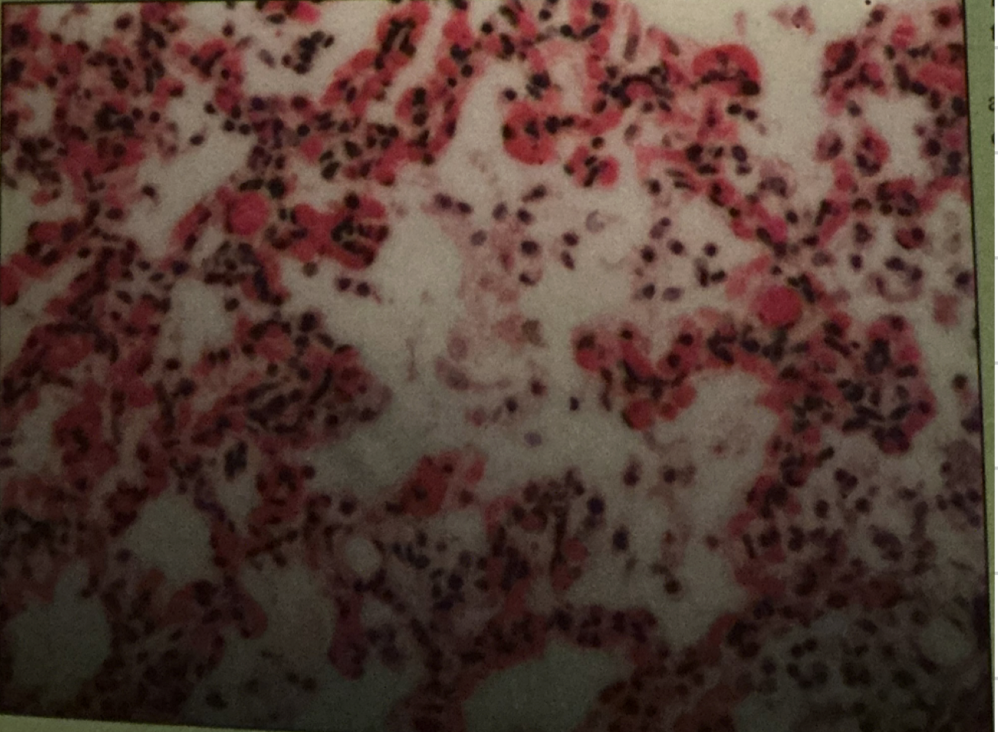

pneumonia

inflammatory lungs; caused by bacterial or viral infection; gas exchange w/ blood decrease; too low oxygen in blood, cellular metabolism can’t progress

pneumonia